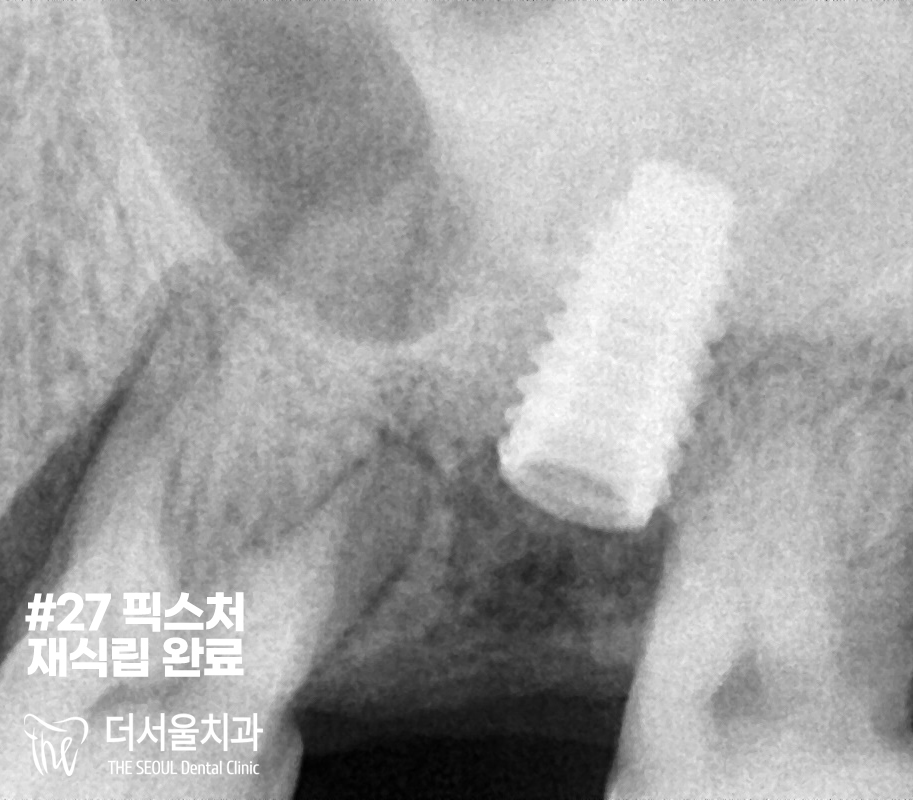

『재수술』

재수술이기에 서현역치과 의료진은

좀 더 신경써서 픽스처를 심었습니다.

그 후, 양쪽 본을 뜨고

그대로 가셨습니다.